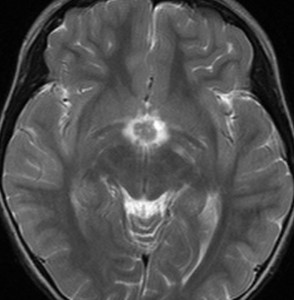

血清HCG-beta 4.5mIUで,下のMRIに見られるように第3脳室(視床下部)のグリオーマ(毛様細胞性星細胞腫)と見間違うような腫瘍でした。下垂体柄は太くなっていないし下垂体のサイズも普通です。もちろん水頭症もありませんので,開頭手術で生検をしてgerminomaの診断を得ました。

上のMRIで視神経交叉が腫大しているのが解りますが,下のMRI CISS画像では更に明らかです,左右の視神経と視交差と視索が腫大していました。視力を計ったら,右0.6,左1.5でいびつな視野欠損がありました。腫瘍はのう胞形成しながら左の視床下部から大脳基底核にも浸潤していました。